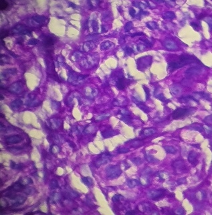

HISTOPATHOLOGY

Fig shows an endoscopic biopsy from a 54 year old individual. Identify the anatomical part of the intestine. What is the pathology. With what clinical symptoms do these patients present? (see surface epithelium)